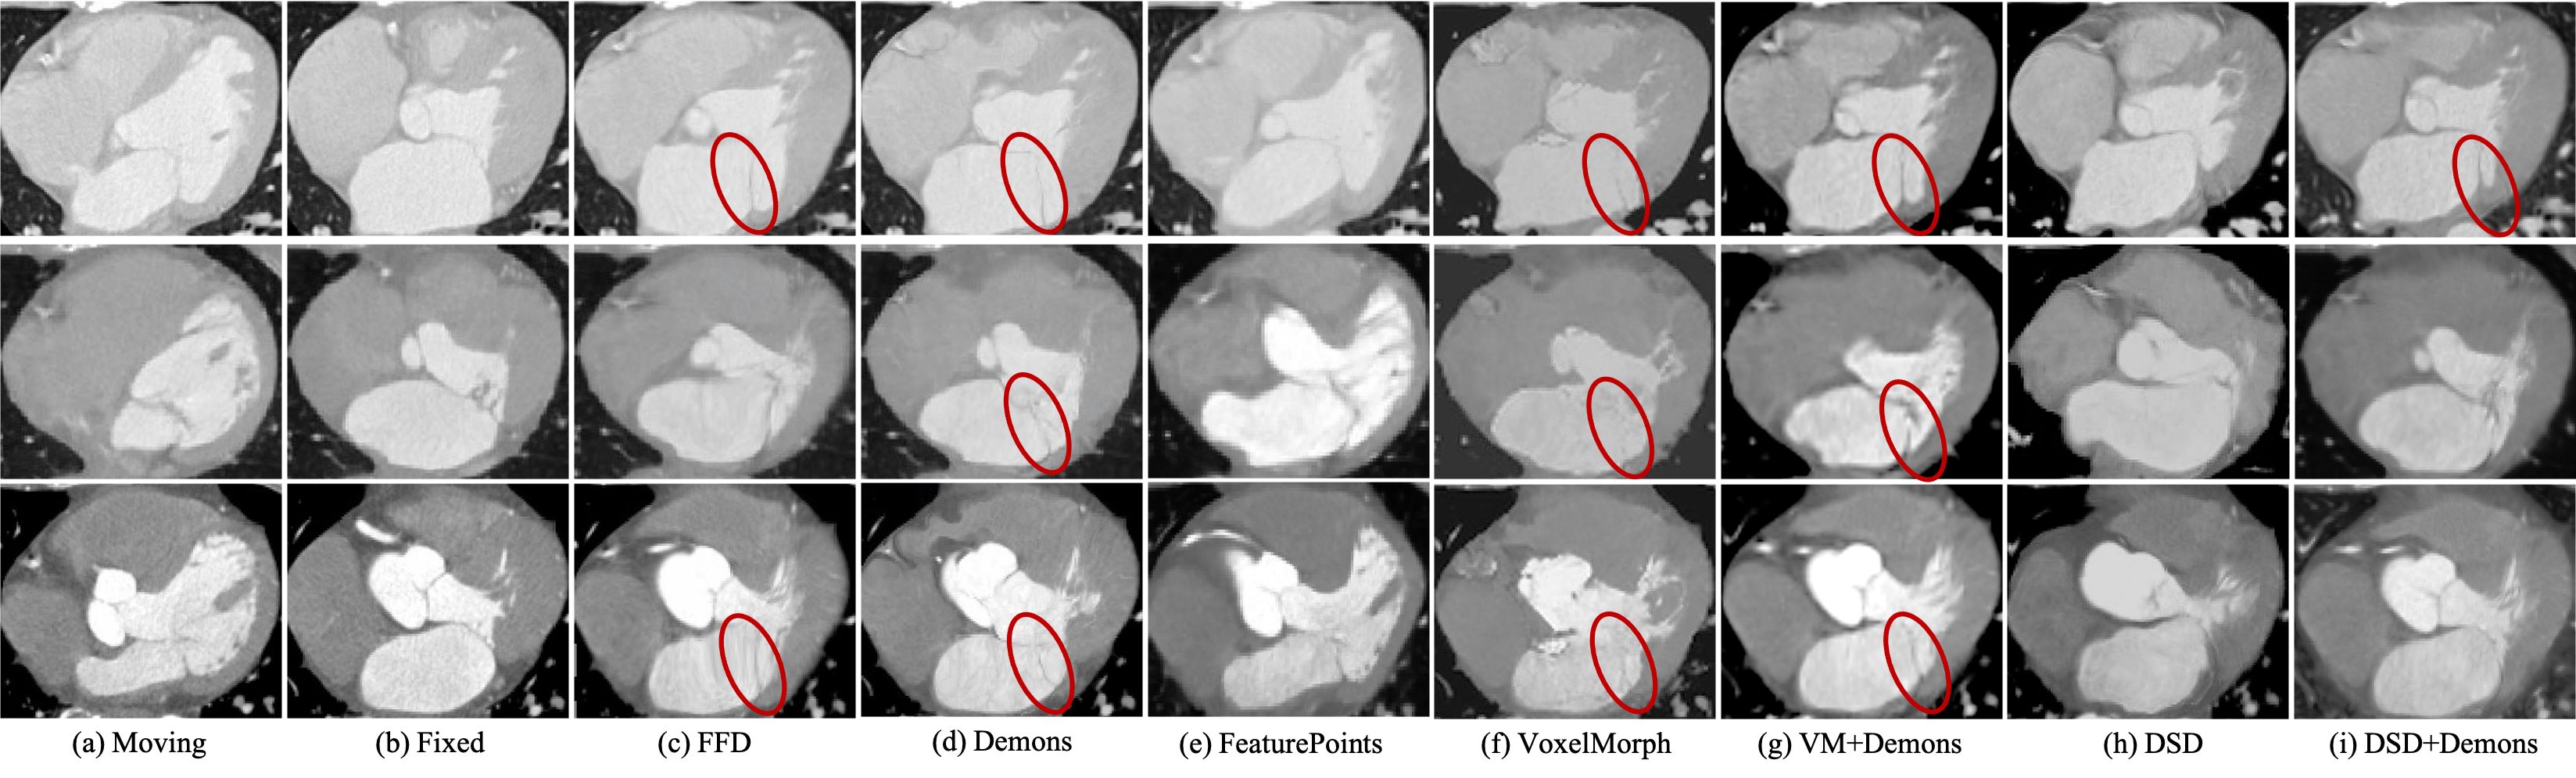

Refer to caption

Figure 8: Visual results of three samples from 4D-C-CT. (a) and (b) indicate the input paired images. (c) - (h) indicate the deformed moving images estimated from the comparison methods. The red circle describes the region associating with folding artifacts and error estimations.

As highlighted in Fig. 8, where FFD and Demons are prone to errors for the images with large motion, which may result in folding in image deformation. The deep-learning-based VoxelMorph slightly alleviates the error deformation, but there are problems in underestimating the deformation as in Fig. 8. In contrast to these methods, our proposed method first extracts landmarks to represent the topological structure of the target organ and estimates the dense motion field by considering the dynamic changes of the organ’s morphology. While our DSD exhibits the great capability of modeling the large motion from detected landmarks, the local appearance must be considered for subtle refinement of the motion field.